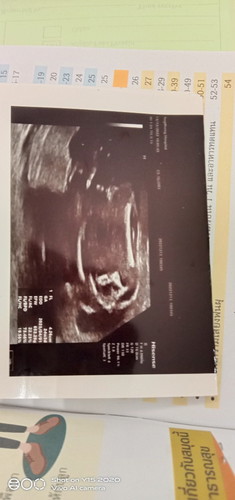

อยากรู้ว่ารูปนี้คือระบุเพศใช่มั้ย

เพศอะไรค่ะ

ช่วยดูให้หน่อยว่าเพศไหน